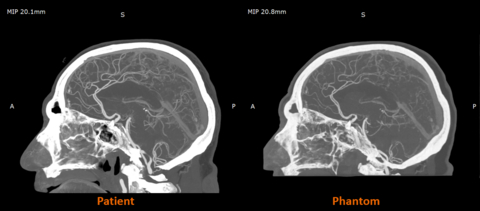

Ранние совместные работы Stratasys и Siemens Healthineers показывают, что RadioMatrix может соответствовать этим значениям с невероятной точностью. По данным компании, в некоторых тестах отклонения составляли всего одну единицу HU. Это означает, что сканеру практически невозможно отличить напечатанную модель от реальной человеческой ткани. Такая точность редко встречается среди синтетических фантомов и является главным преимуществом RadioMatrix.

Сравнение изображения пациента и фантома. Изображение предоставлено Stratasys.